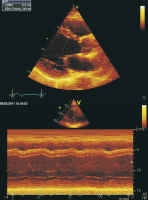

Echokardiographie aktuell: Basis- und erweiterte Evaluierung der systolischen Linksventrikelfunktion nach Myokardinfarkt

Journal für Kardiologie - Austrian Journal of Cardiology 2011; 18 (3-4): 102-104 Volltext (PDF) Abbildungen mit Filmsequenzen